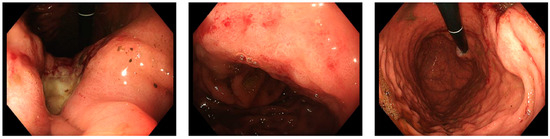

2. Case Report

2.1. Patient History and Staging

2.2. Multimodal Approach and Treatment